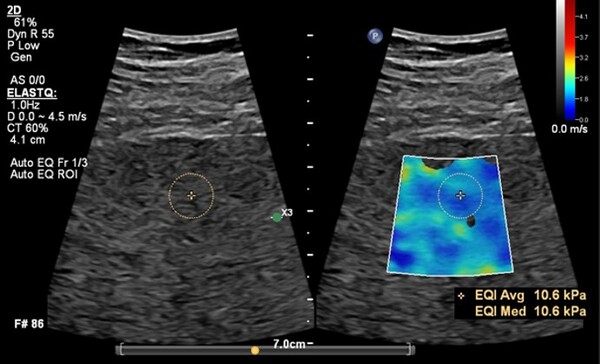

필립스의 ‘오토 엘라스트큐’ 기능은 전단파 탄성 초음파(Shear Wave Elastography, SWE) 데이터를 자동으로 분석하고 최적의 측정 프레임과 검사 관심 영역(ROI, Region of Interest)을 설정하는 기능으로 검사 효율성과 진단 정확도를 향상한다.

기존에는 의료진이 수동으로 프레임과 ROI를 지정해야 했으나, 이제는 시스템이 자동으로 최적의 측정 위치를 설정하여 더욱 빠르고 정밀한 검사가 가능하다. 이를 통해 검사 시간이 기존 대비 60% 단축되고, 키 스트로크(조작 횟수)가 29% 감소해 의료진의 업무 부담을 줄이는 데 기여한다.